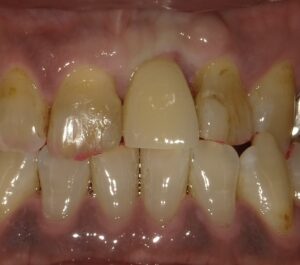

上部構造が装着されたところです。